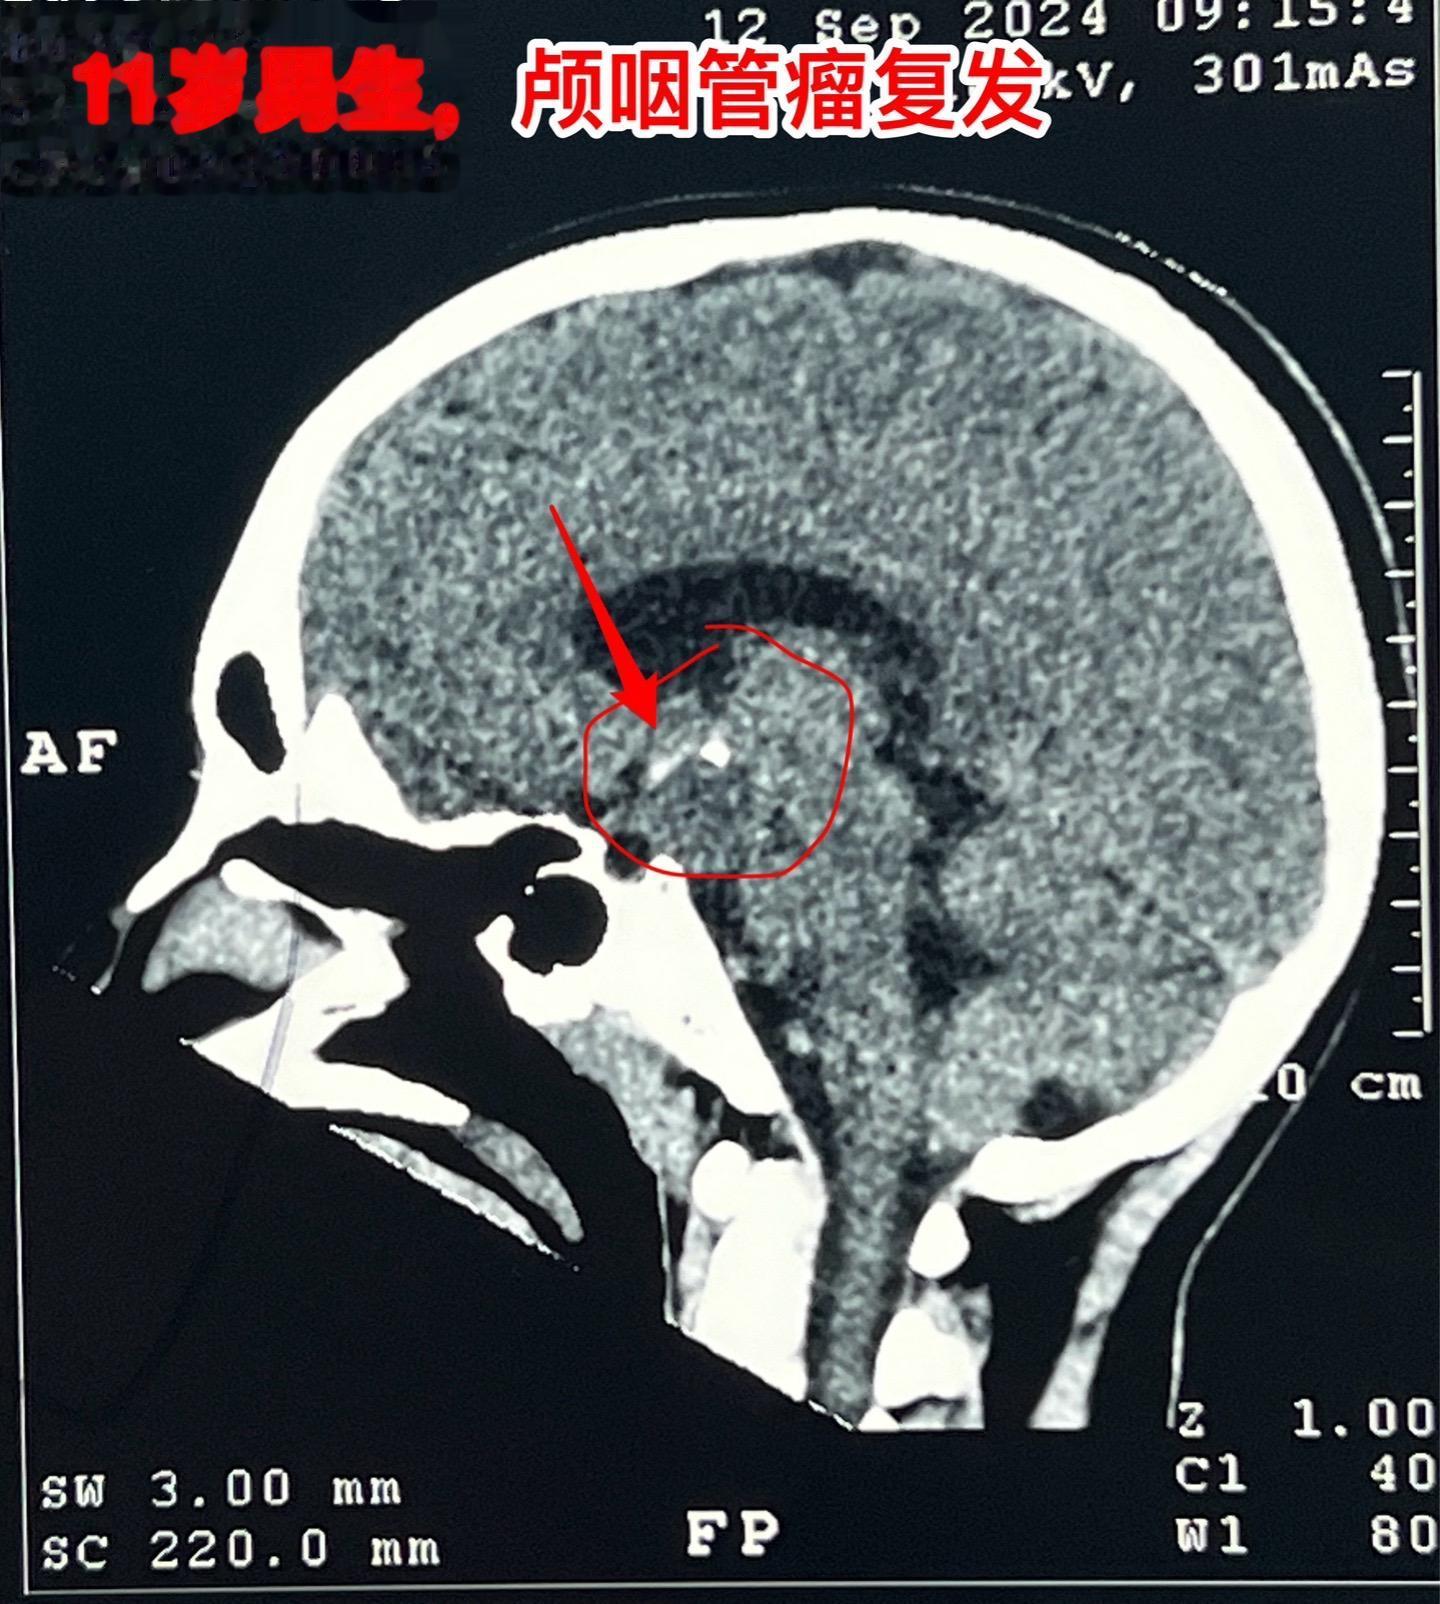

国庆节长假后第一天完成两个手术。一个手是33岁女性,来自云南省香格里拉。因左眼视力下降,到医院检查发现鞍区肿瘤,怀疑是颅咽管瘤。病人没有内分泌功能障碍。影像学上肿瘤是实性的,没有钙化,而且可以看见垂体信号。到底是什么肿瘤呢?今天手术中取肿瘤标本作快速冰冻病理检查,报告是垂体瘤。肿瘤得到完全切除,手术后病人视力好转了。 另一个手术是11岁男孩子,颅咽管瘤复发。经原切口翼点入路将肿瘤完全切除。术前磁共振只看见一个圆形肿瘤,术中发现除了这个肿瘤外还有5个散在的钙化斑,均得到完全切除。这样的散在钙化斑是潜在的危险因